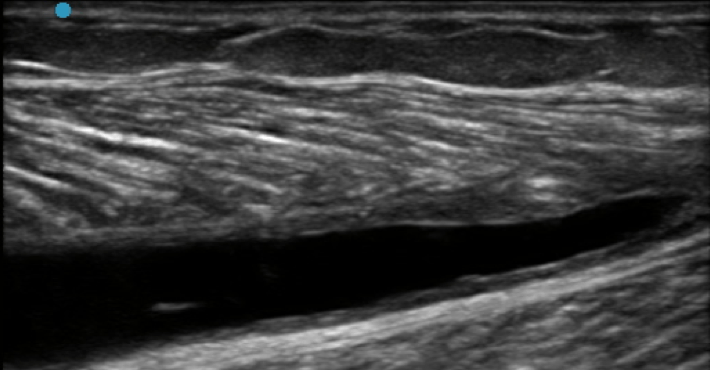

Rotura muscular gemelo medial, llamada TENNIS LEG

Tennis Leg con hematoma miofascial